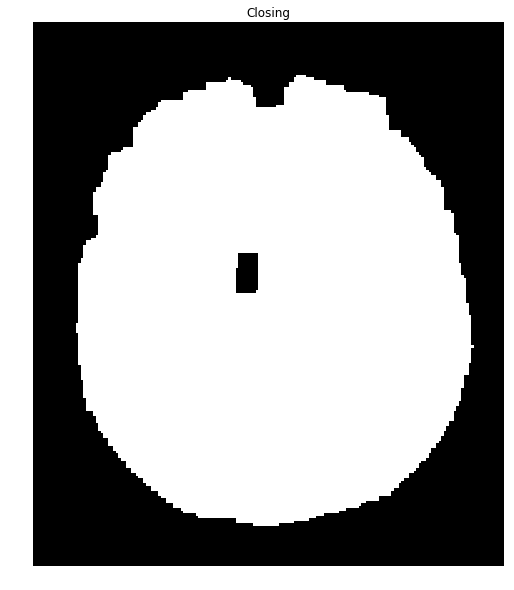

Running this again with your second image produces a mask with many holes:

We can close many of these holes using a closing transformation):

brain_mask = np.uint8(brain_mask)

kernel = np.ones((8,8),np.uint8)

closing = cv2.morphologyEx(brain_mask, cv2.MORPH_CLOSE, kernel)

ShowImage('Closing', closing, 'gray')